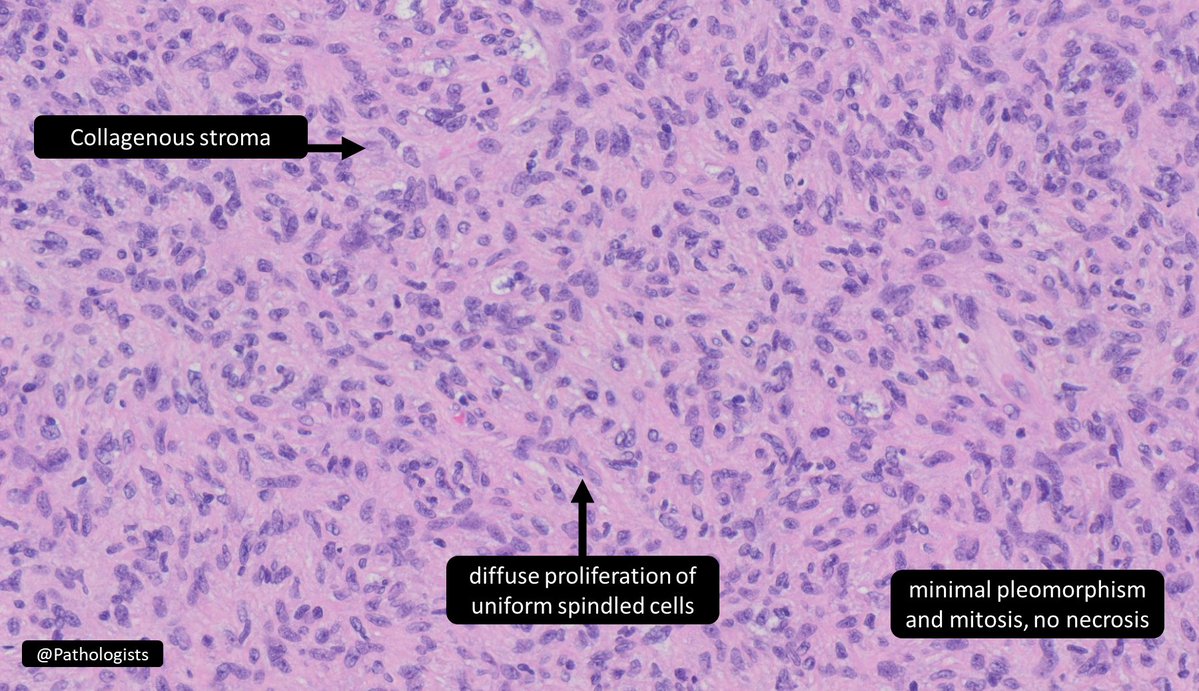

Endometrial stromal ___ a) nodule b) sarcoma 🔬@Pathologists https://t.co/1z7GBOsejY #GYNPath #PathTwitter #Pathology #BSTPath